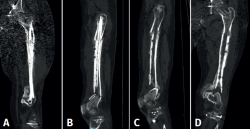

Figura 3. En las imágenes A y B puede observarse la consolidación de la fractura en el fémur proximal. En las imágenes C y D se aprecia la consolidación proximal de la fractura del fémur, así como la consolidación parcial viciosa en el fémur distal. Debido a las consolidaciones que se muestran, no se aplicó ningún método de estabilización entre una cirugía y otra.